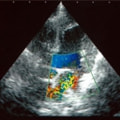

C:超音波画像 肺動脈領域の異常血流

D:左心系の拡張による二次的僧帽弁逆流

症例:【マルチーズMix 1歳齢 メス】

左側胸壁よりLevine 4/6の連続性心雑音が聴取された。胸部レントゲン検査において心拡大が認められ、超音波検査においても肺動脈領域に連続的な異常血流が観察された。大学病院を紹介受診され、手術が行われた。現在はACE阻害薬のみの内服で補助的治療を行っている。